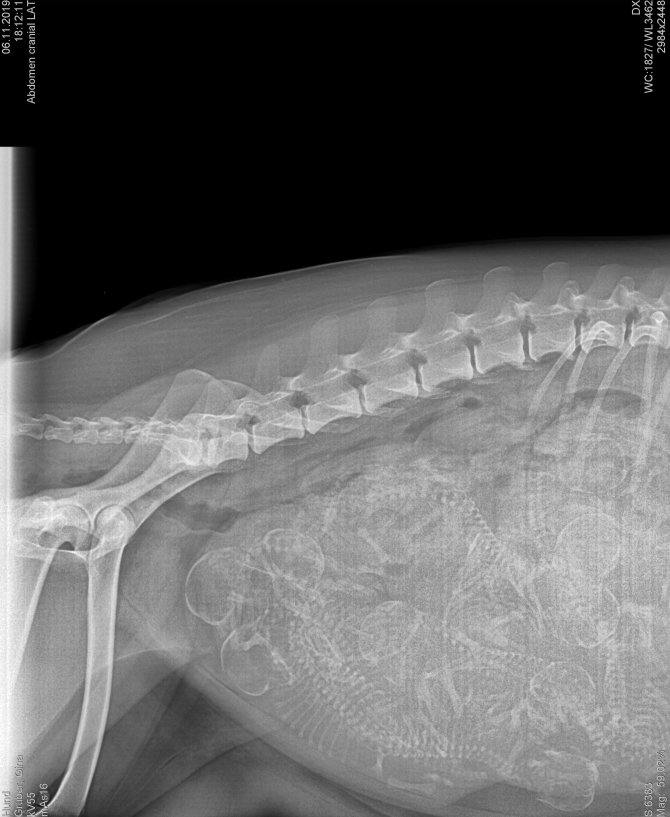

6.11.2019 Erster "Blickkontakt" (Röntgenbild)